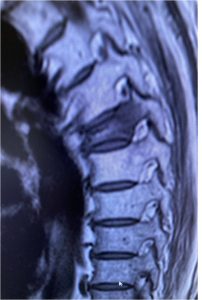

Εικόνα 3 (α,β,γ,δ,ε,): Η Μαγνητική τομογραφία αποκαλύπτει την ύπαρξη κατάγματος του 6ου Θωρακικού σπονδύλου. Με την καθοδήση του συστήματος πλοήγησης O-Arm πραγματοποιήθηκε η προώθηση των ειδικών trocar διαυχενικά εντός των σπονδυλικών σωμάτων μέσω των οποίων έγινε η έγχυση Polymethylmethacrylate (P.M.M.A.) στο σπονδυλικό σώμα αμφοτερόπλευρα ενώ είχε ήδη ληφθεί οστικό υλικό για βιοψία.

Εικόνα 3 (α,β,γ) : Προεγχειρητική Μαγνητική Τομογραφία, πλαγία λήψη ακολουθία Τ2, καταστροφή του οσφυϊκού σπονδύλου συνεπεία μετάστασης από το μυελό. Δια κυφοπλαστικής (β,γ) πραγματοποιήθηκε αποκατάσταση του σπονδυλικού σώματος.